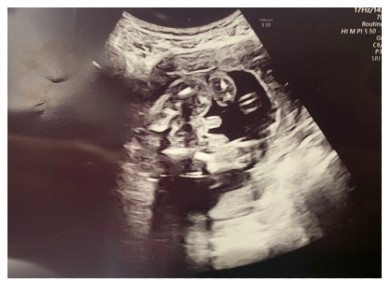

フジテレビ系バラエティー番組「あいのり」に出演していたブロガーの桃さんが1月5日、妊娠中の第1子の性別をブログで発表。エコー写真を掲載しながら、男の子であることを報告しました。

桃さんは、2020年6月に6歳年下の男性と結婚。12月4日にブログで第1子妊娠を報告しており、2021年5月に出産予定であることを伝えていました。